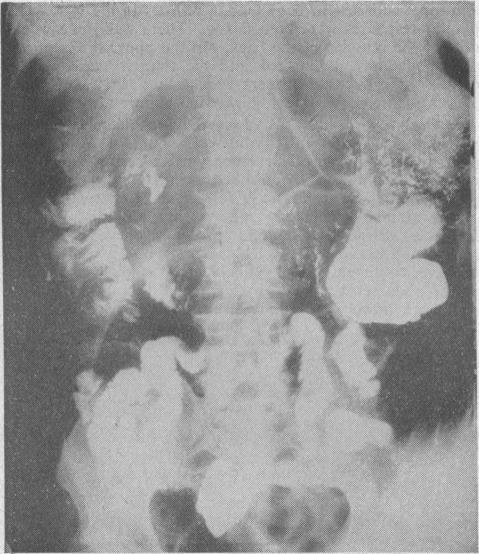

Acute enteritis with temporary intestinal malabsorption.

Br Med J. 1960 Apr 30;1(5182):1324-7. doi: 10.1136/bmj.1.5182.1324.